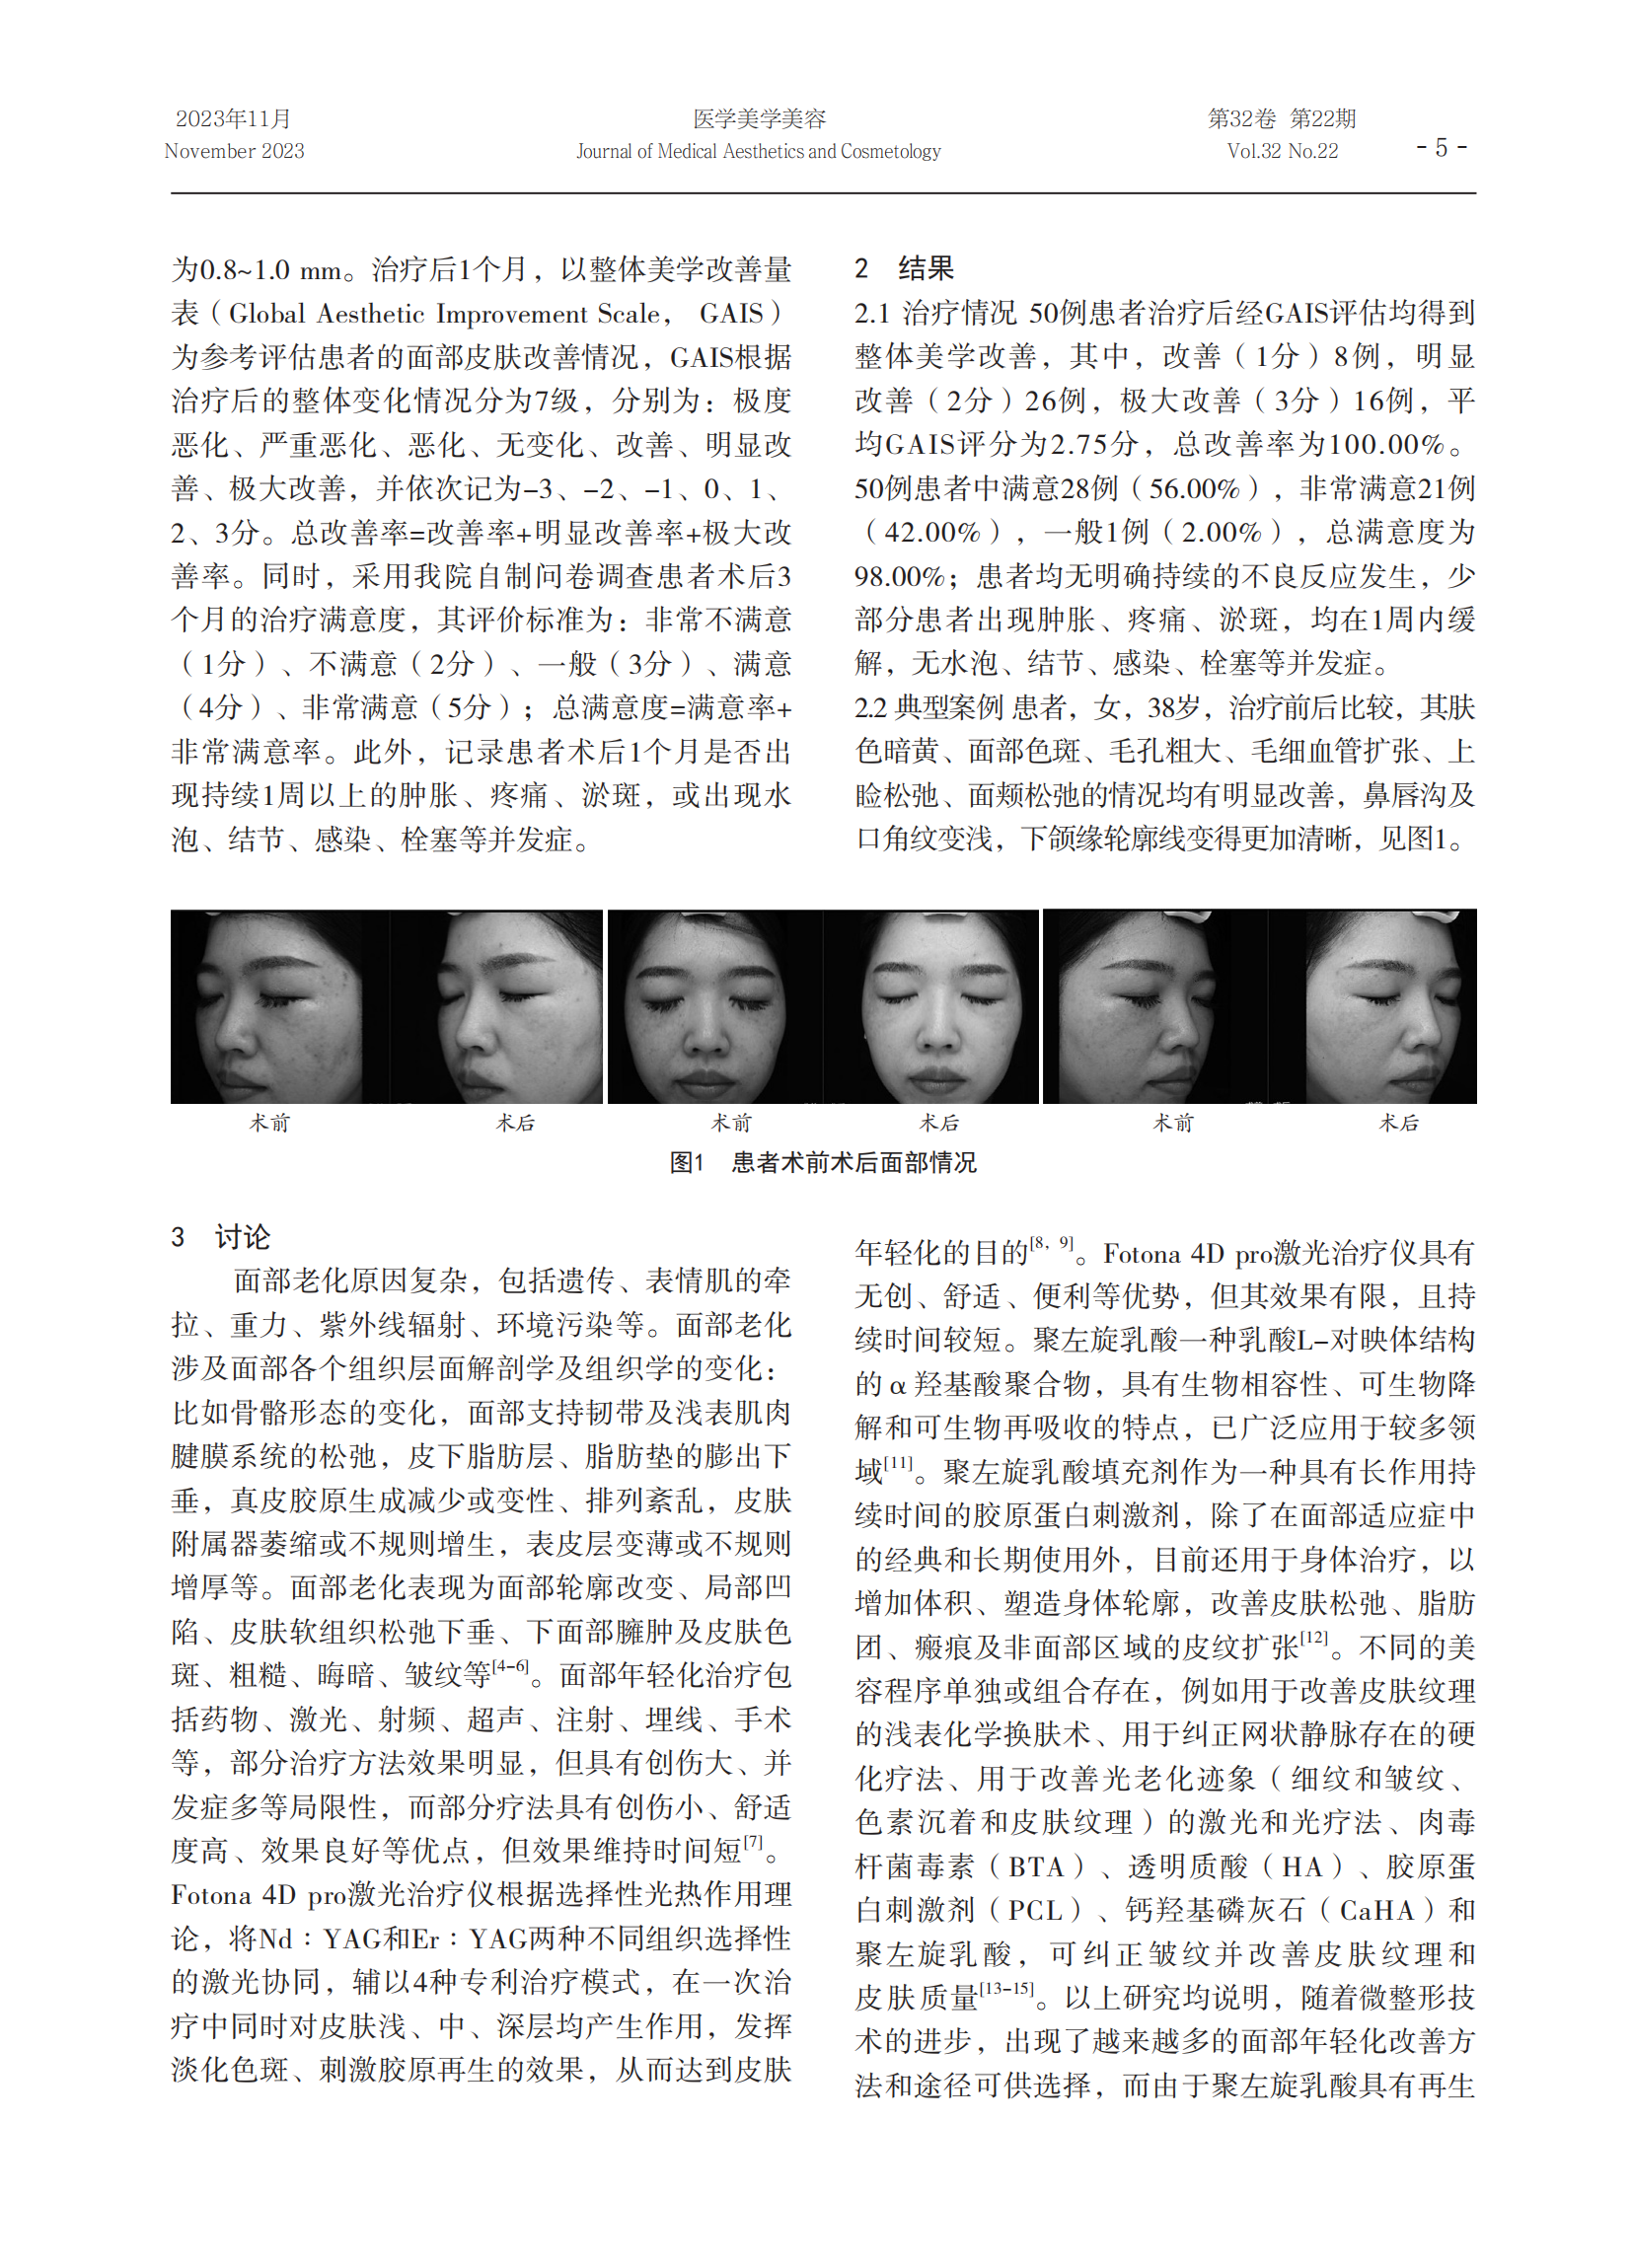

乳酸是葡萄糖或糖原经过糖酵解无氧代谢过程的最终产物。长期以来,乳酸被广泛认为是导致运动能力下降和运动疲劳的代谢废物。然而,近年研究发现,乳酸在机体中具有重要作用:1)乳酸作为能量底物和糖异生前体,不是导致代谢性酸中毒的原因,反而起到缓冲作用;2)乳酸穿梭作用于靶向部位,发挥细胞间信号传导的信使作用;3)乳酸既是脑的重要能源物质,又可以介导运动改善认知和记忆的过程。